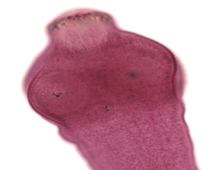

Diphyllobothrium latum

This is a gravid proglottid of a ________________.